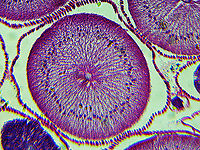

Roundworm Uterus Cross-section (Female) - Ascaris lumbricoides

*Microscope slide; cross-sectionhttps://www.jungledragon.com/image/118183/roundworm_female_with_labels_-_ascaris_lumbricoides.html